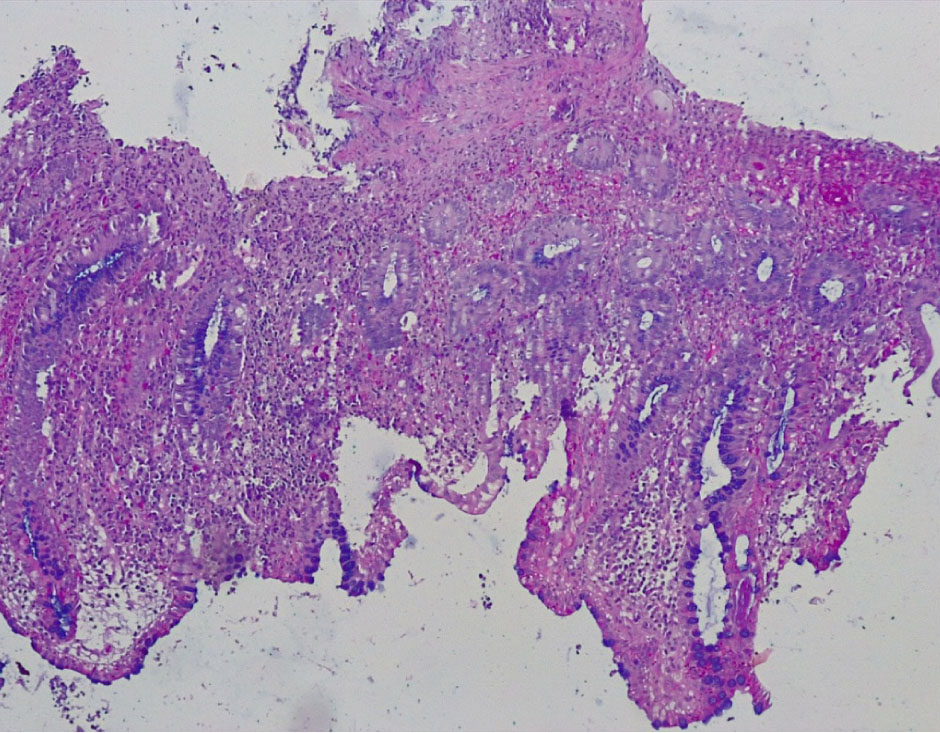

В основной группе морфологические и гистохимические изменения в СО толстой кишки были представлены язвами, нарушением регенерации цилиндрического эпителия и крипт, атрофией бокаловидных клеток, снижением продукции муцина клетками эпителия, различной степенью выраженности воспалительной реакции.

Язвенные дефекты СО толстой кишки были неглубокие и достигали собственную и мышечную пластинки. Вокруг язв отмечалась умеренно или резко выраженная лимфо-плазмоцитарная инфильтрация стромы с примесью нейтрофилов (++, +++), со сдавлением клеточным воспалительным инфильтратом крипт и развитием атрофии цилиндрического эпителия и крипт (++) (рис. 3).

Рис. 3. Основная группа: в СО толстой кишки – язвенный дефект с резко выраженной лимфоплазмоцитарной, нейтрофильной инфильтрацией, атрофией крипт и бокаловидных клеток. Окр. гематоксилином-эозином, ×200

В отдельных группах крипт отмечалось выраженная атрофия бокаловидных клеток (БК) (не более 3–4 на крипту) вплоть до полного их исчезновения (+++), развитие очагов гнойного криптита за счет выраженной нейтрофильной инфильтрации вокруг крипт (рис. 4).

Рис. 4. Основная группа: неравномерная атрофия крипт и бокаловидных клеток СО толстой кишки, выраженное хроническое воспаление стромы со скоплением нейтрофилов в отдельных криптах (гнойный криптит). Окр. гематоксилин-эозином, ×200